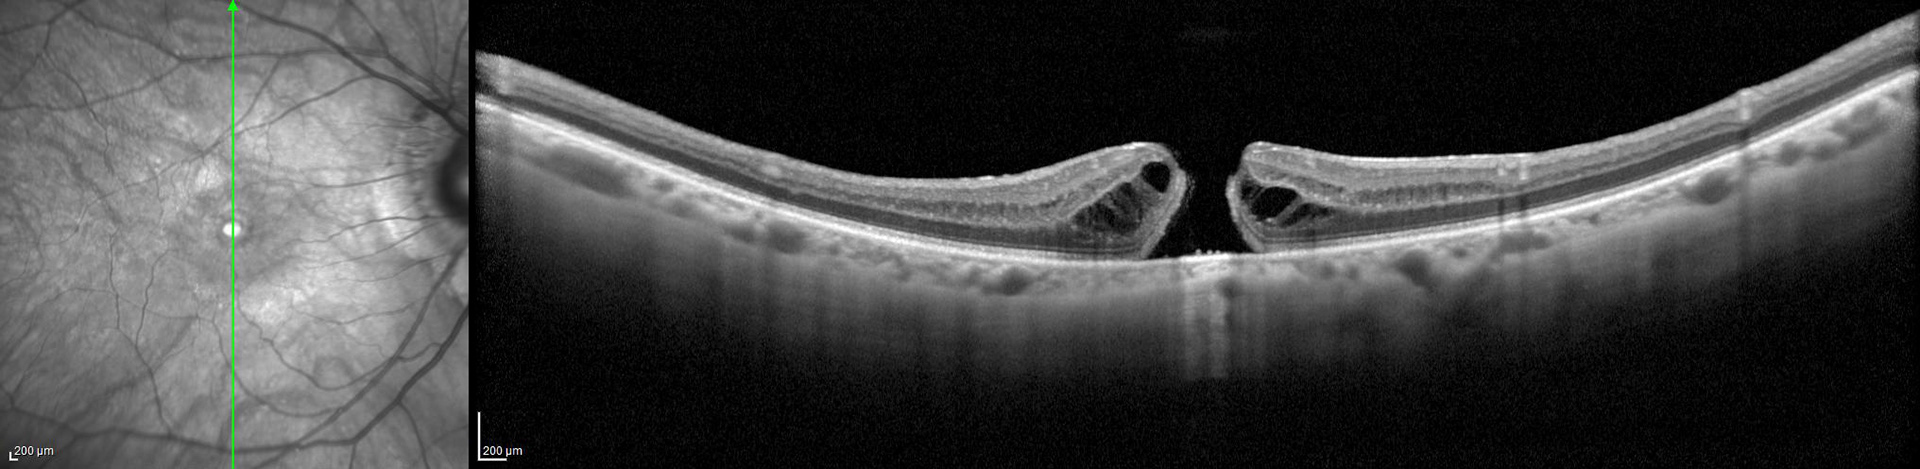

Mención de honor: Agujero Laminar en la categoría Tomografía de Coherencia Óptica